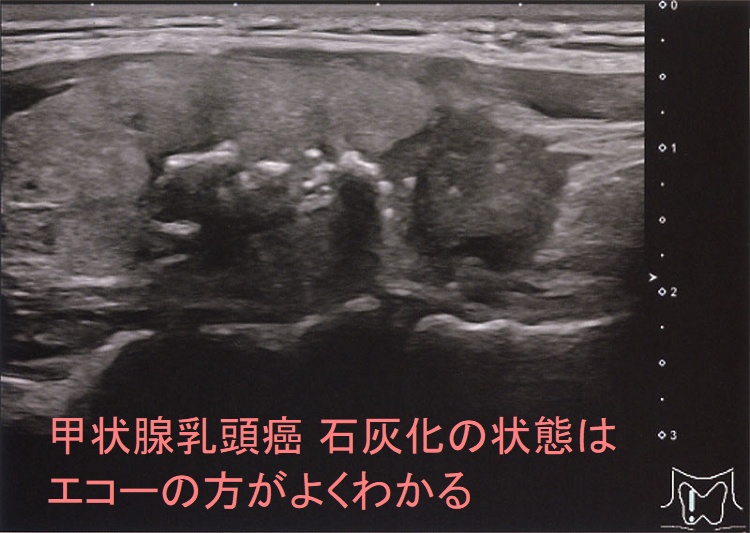

- 精密でも5mm、通常10mmスライスで撮影するため、解像度が悪く、5-10mm以内の病変が写らない確率が高い[甲状腺超音波(エコー)検査は、3mm大(条件次第では2mm大)の甲状腺癌でも見つかります。また、甲状腺乳頭癌において最大の特徴である微細な砂粒状石灰化(psammoma body)は5mm未満のため、CT・MRIでは写りません。]

同時に、CTでは甲状腺癌の微細石灰化(5mm以下)が写らない。さらに、細かい石灰化の状態を評価できない。